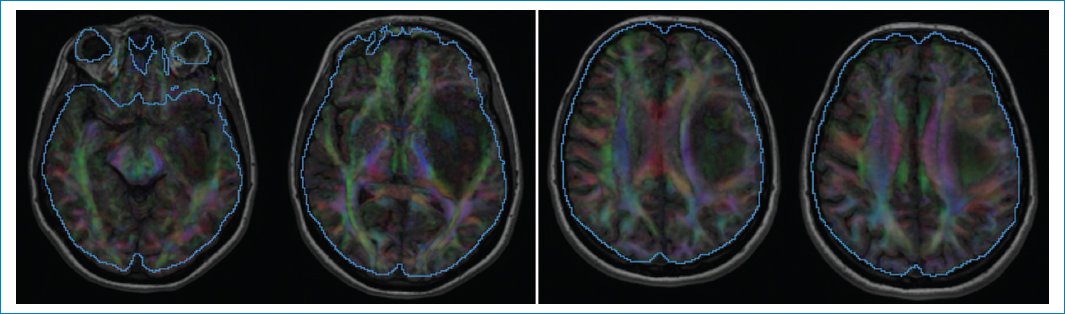

La secuencia de difusión aporta un ADC diferente en la periferia de la neoplasia (0,69 × 10–3 mm2/s) (Fig. 5), que es bajo, indicando mayor celularidad, y es alto en el centro (1,75 × 10–3 mm2/s)5,6. Este último valor refuerza la hipótesis de un IDHm y no codeleción de 1p/19q. Lo mismo ocurre con los valores obtenidos en la medición de la anisotropía fraccional, la difusión paralela y la difusión perpendicular79 (Fig. 6).

Figura 6. Tensores de difusión. FA = 0,075 (n = 0,21). Difusividad paralela = 1,45 (n = 1,21). Difusividad perpendicular = 1,29 (n = 0,91).